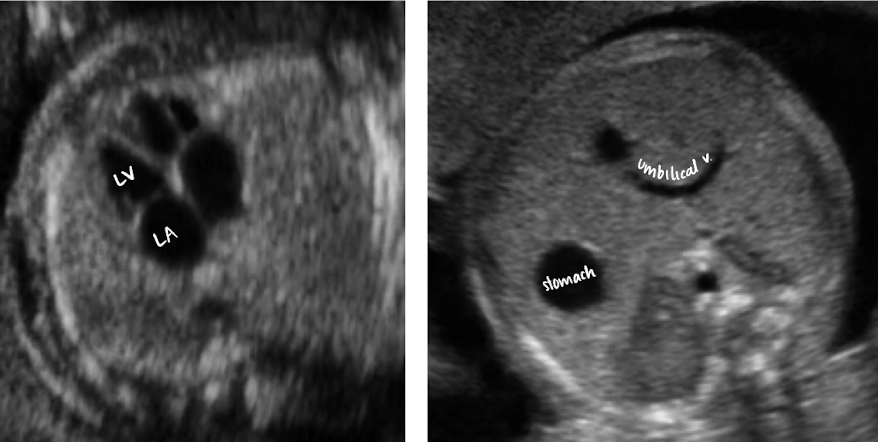

imaging the 4-chamber heart

obtained from TRV view of abdomen just above diaphragm

make sure to have ribs on both sides during 4CH view

must see ribs on both sides to be true TRV rather than oblique

heart takes up 1/3rd of chest

heart angles 45 degrees to the left

always make sure the heart is beating